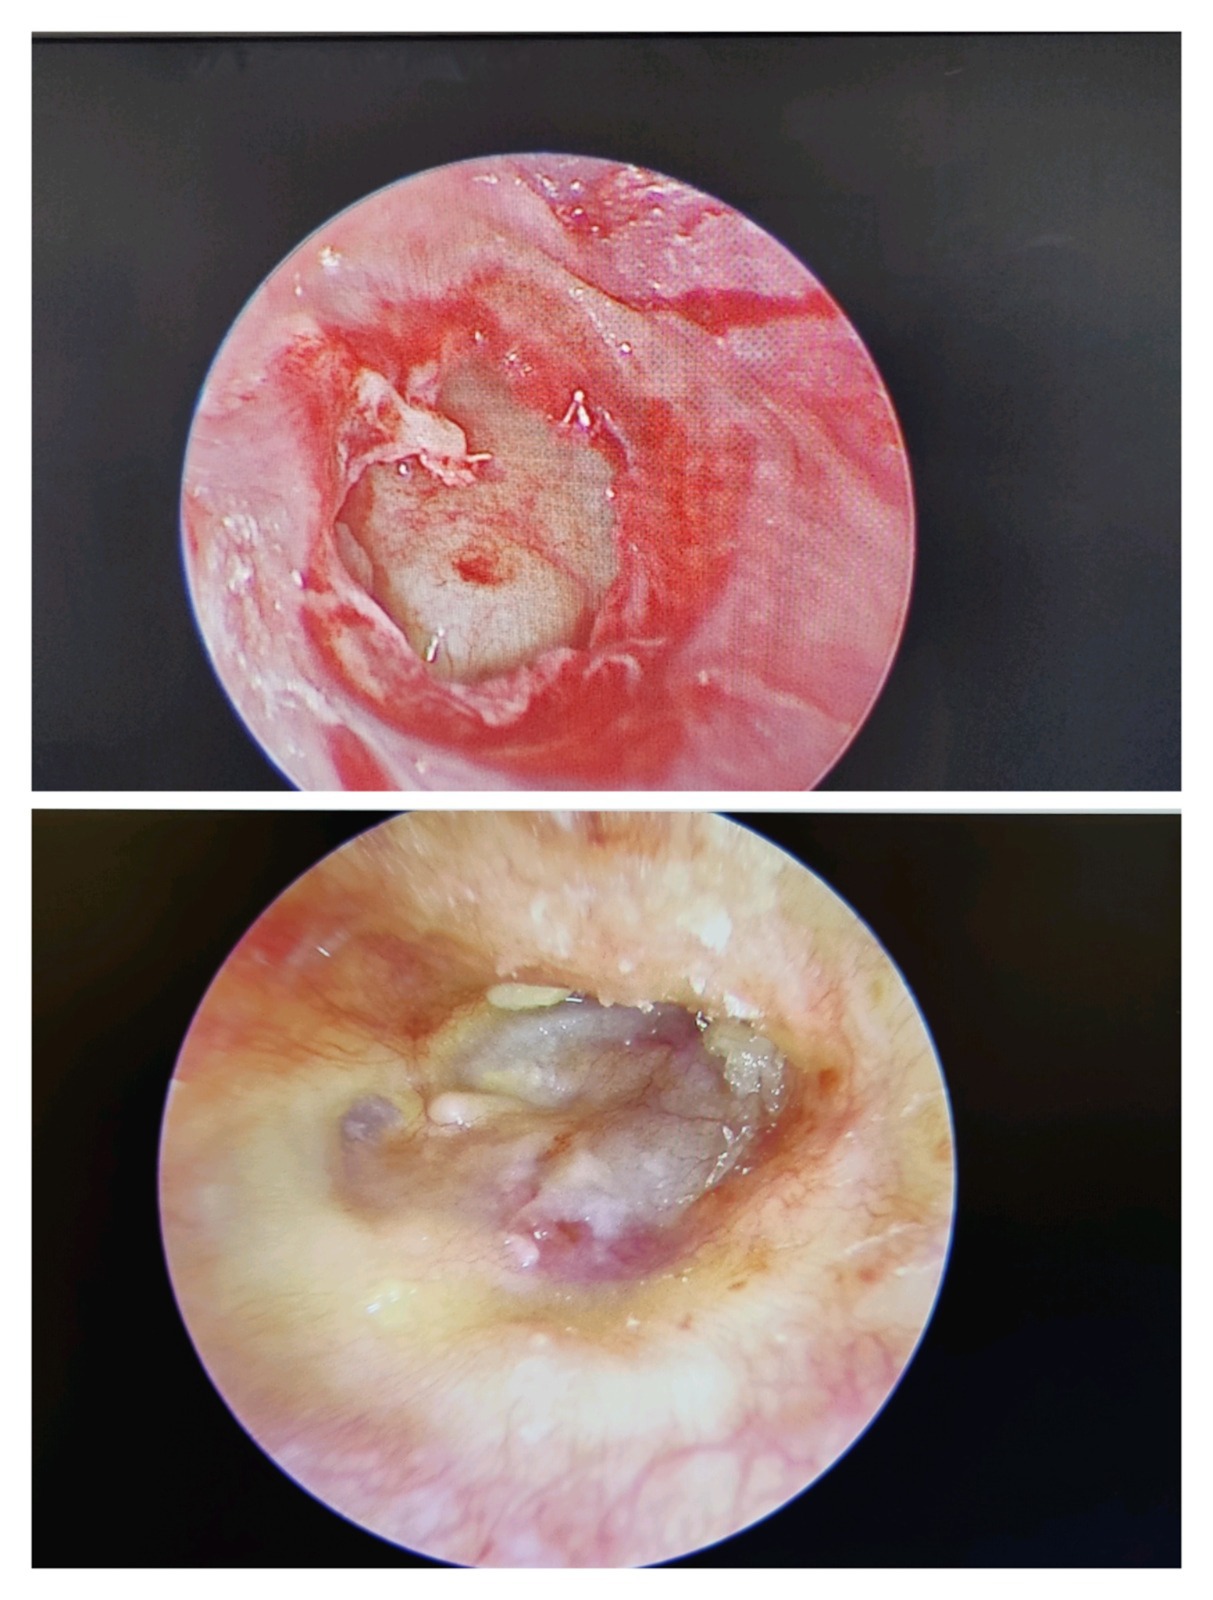

1. Tympanoplasty (Eardrum Repair Surgery)

Tympanoplasty repairs a perforated or damaged eardrum using advanced microscopic techniques.

2. Stapedotomy (Otosclerosis Hearing Surgery)

Stapedotomy is performed when the stapes bone becomes fixed due to otosclerosis, causing hearing loss.

Dr. Muddazir replaces the fixed stapes bone with a prosthetic, restoring natural sound conduction.

3. Ossiculoplasty (Middle Ear Bone Reconstruction)

Ossiculoplasty reconstructs or replaces damaged ossicles (hearing bones: malleus, incus, stapes).